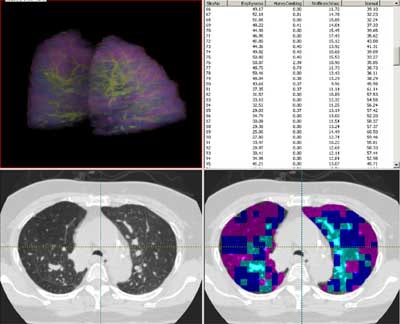

| Screen shot in Pulmonary Analysis Software Suite (PASS) shows a lung that has been color-coded for parenchymal characteristics assigned by the adaptive multiple feature method. |

![]() |